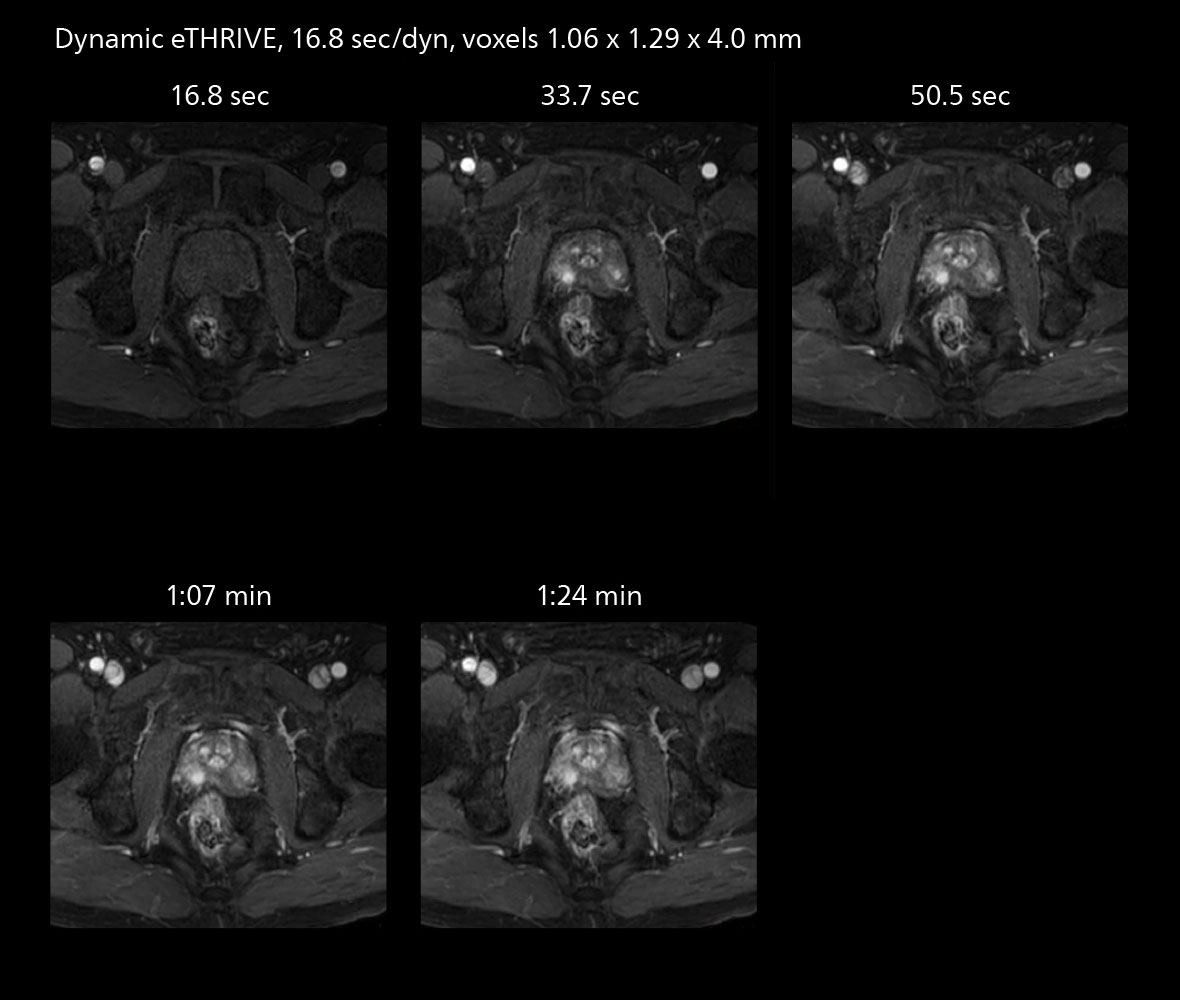

MRI of prostate

Examples of prostate imaging showing faster scan times and improved resolution illustrate the power of SmartPath to Elition X in this case of prostate cancer with PI-RADS score 4.

The high performance of the Vega HP gradients is particularly impressive in DWI. “The Vega HP gradients enable us to scan faster and use b-values as high as 2000, for example in prostate DWI and in DWIBS, which provides image quality that is remarkably improved over the previous system and we are able to more easily see lesions.”